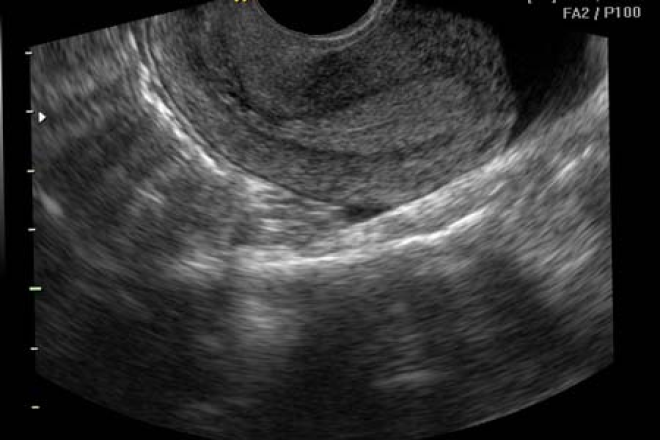

Útero

Es una víscera muscular hueca, paredes gruesas, forma de pera, destinado a la implantación del huevo fecundado y a expulsarlo cuando éste ha alcanzado su desarrollo completo, así como a la descamación mensual del endometrio (menstruación).

Esta situado en la pelvis menor entre la vejiga por delante y el recto por detrás, por arriba de la vagina y por debajo de las asas intestinales.

Esta aplanado de adelante a atrás de base superior y vértice inferior, presentando en la unión de su tercio inferior con sus dos tercios superiores un estrechamiento llamado istmo, que lo divide en una porción superior o cuerpo y una inferior o cuello.